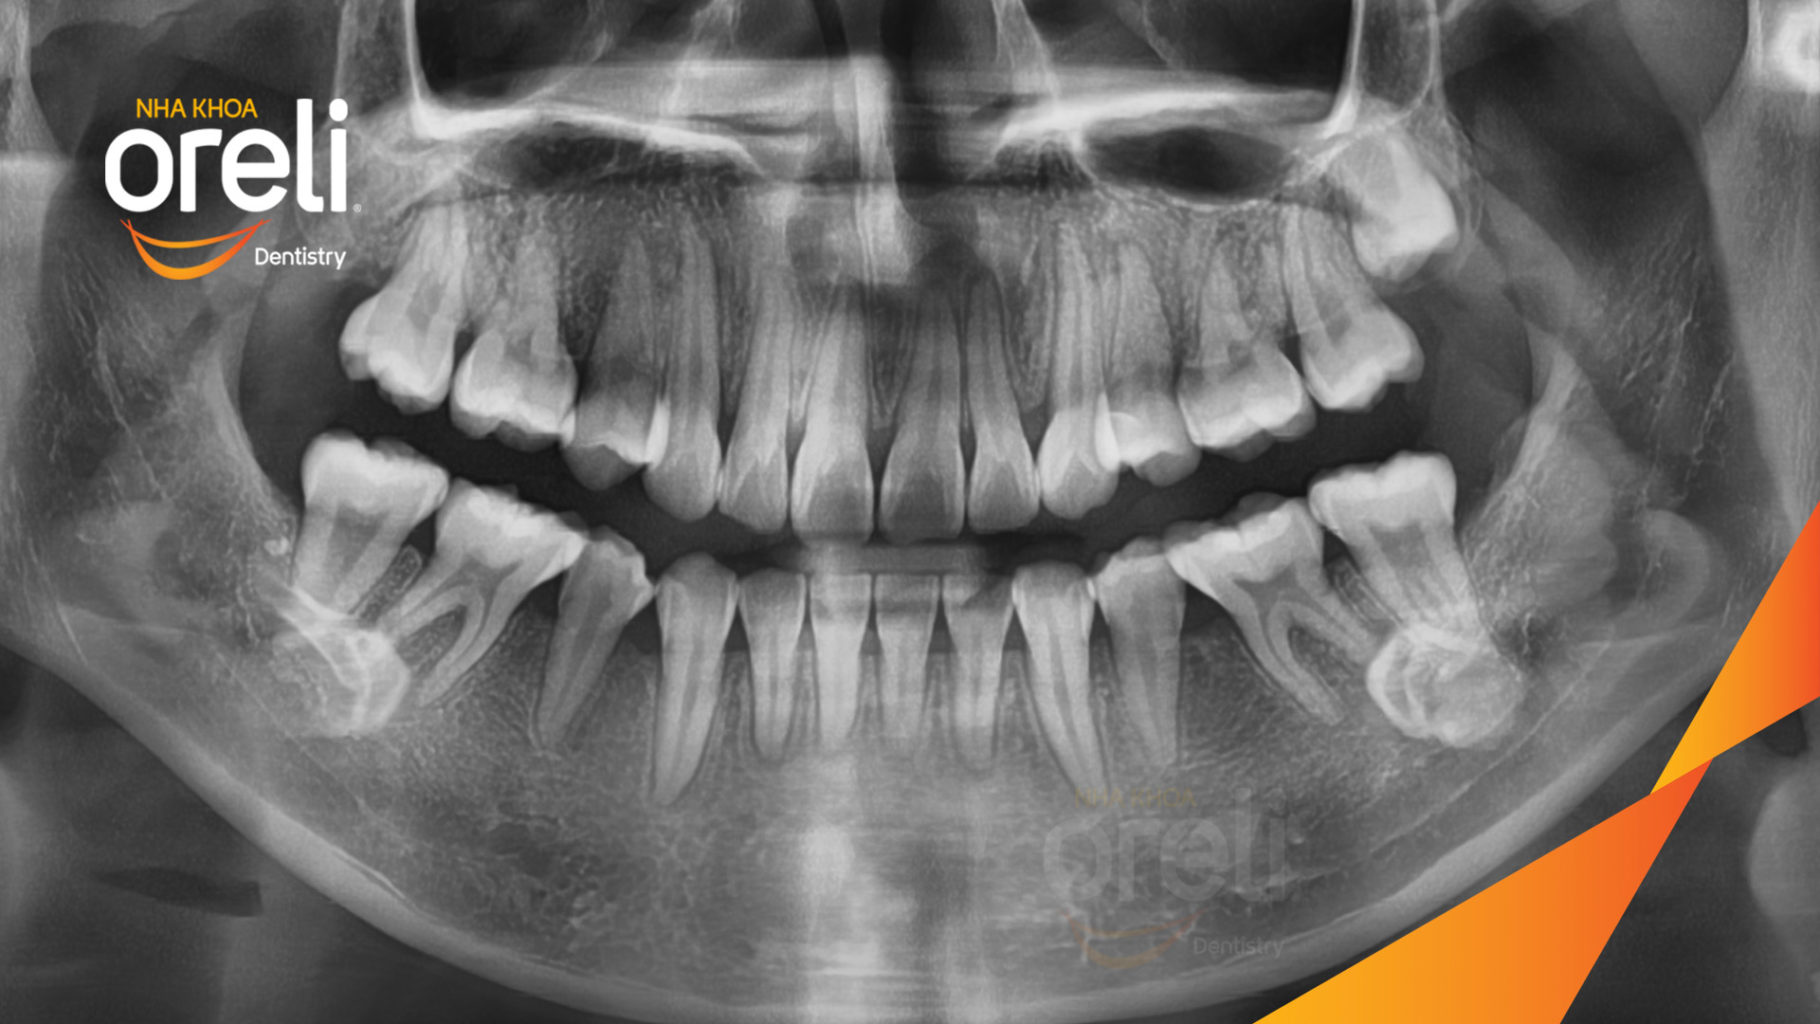

Ca niềng chỉnh chen chúc hẹp hàm nặng cả trên và dưới – Kết quả điều trị thực tế tại nha khoa Oreli

Ca niềng răng chen chúc phục hồi ăn nhai và thẩm mỹ nụ cười. Kết quả thực tế trước và sau điều trị tại Nha khoa Oreli.

Hình ảnh thực tế